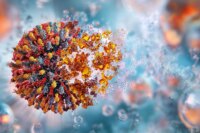

AI-Designed Universal Vaccine: A Solution to Future Pandemics

Summary of This AI-Designed “Universal Vaccine” Could Stop Future Pandemics Before They Start: A new AI-designed universal coronavirus vaccine has successfully passed its first human trial, demonstrating safety and promising…